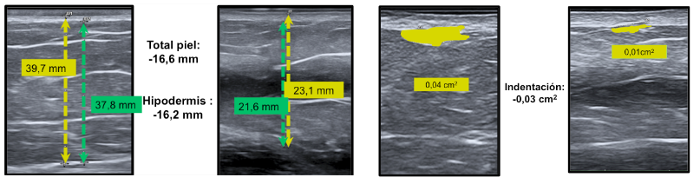

Más concretamente, las mujeres en estudio reducen 8,64mm de media el grosor total de la piel (alrededor de un 27%), y 8,77mm de media (un 20%) el grosor de la hipodermis -la capa de la piel encargada de almacenar grasa-. Asimismo, el estudio muestra una menor infiltración de grasa hipodérmica en la capa superior (área de indentación). En este caso, la ecografía muestra al médico de forma transversal las protuberancias que se originan en la hipodermis y presionan las capas superiores de la piel. En éstas se observa una disminución del 33% de su superficie, una reducción muy significativa de la hipodermis y muy destacada por las investigadoras. Todos estos efectos a nivel interno de la piel son los que permiten mejorar el aspecto de la misma en las zonas en tratamiento, tanto a la vista como al tacto.

Ejemplos de ecografías en pacientes